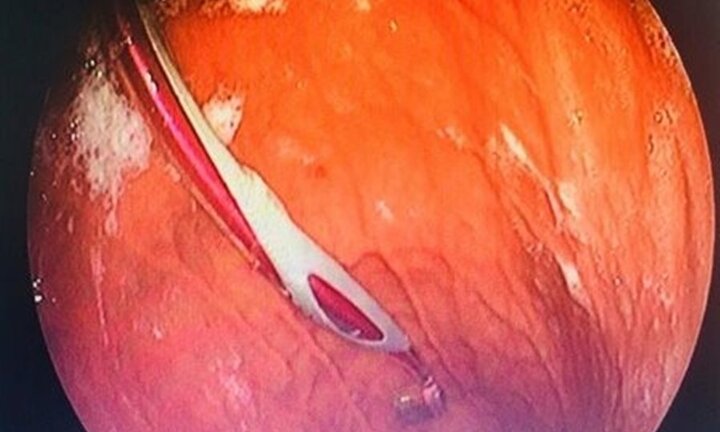

Lấy bàn chải chữa học xương cá, do ngửa cổ cao, người phụ nữ tại Thái Nguyên nuốt luôn bàn chải.